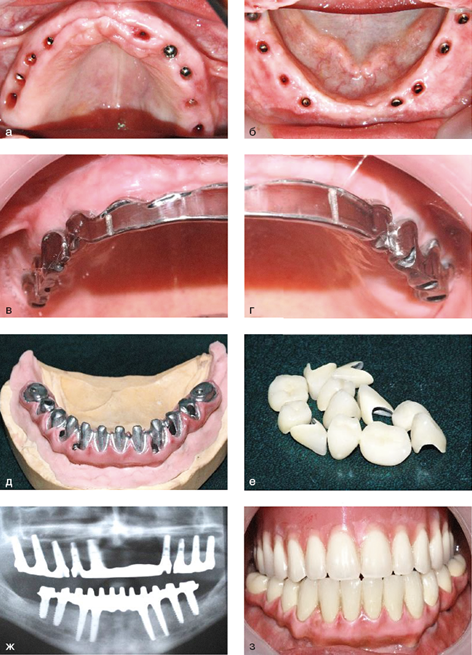

Рис. 2.9.4. Съемный протез на имплантатах на верхней челюсти и несъемный - на нижней челюсти при полном отсутствии зубов: а, б - имплантаты в полости рта; в, г - балка на имплантатах для опоры съемного протеза на верхней челюсти; д, е - металлический каркас на имплантатах для фиксации керамических коронок на нижней челюсти; ж - ортопантомограмма челюстей с балкой и каркасом на имплантатах; з - протезы на имплантатах в полости рта